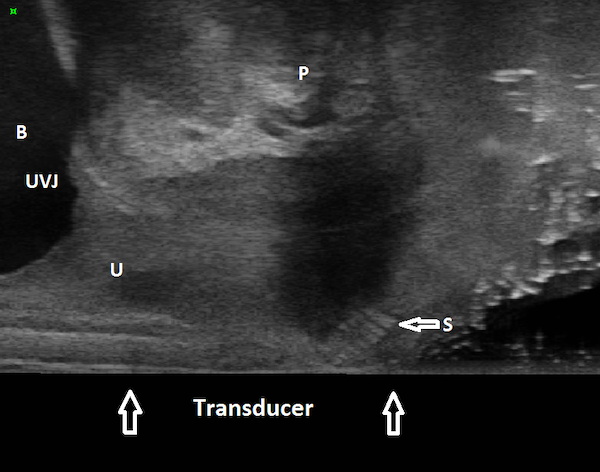

Figures 1, 2, and 3 are mid sagittal plane cut sections of 3D cubes obtained of the anterior pelvic compartment using an endovaginal transducer (BK Profocus Ultraview, Peabody, MA).

Figure 1

Endovaginal 180 degrees anterior compartment image in the midsagittal plane (transducer in the vagina scanning anteriorly): transobturator sling is seen to lie mid-urethrally. B: Bladder; U: Urethra; S: Sling; UVJ: Urethrovesical junction; P: Symphysis pubis

The sling can be seen located mid-urethrally in Figure 1, underneath proximal urethra in Figure 2, and proximal to the urethrovesical junction in Figure 3, a year after surgery. Whether sling location impacts surgical outcome is a matter of controversy. Dietz et al (2004) concluded that variations in sling placement have little effect on symptom resolution and patient satisfaction in a study of 142 women whose outcomes were evaluated 5 weeks to 2.1 years following TVT sling surgery. Using transperineal ultrasound, the tape position in their study was found to vary from 30 mm above to 12.7 mm below the symphysis pubis at rest and between 15 mm above to 18.7 mm below the symphysis pubis on Valsalva. However, in an unmatched case-control study of 100 patients who underwent Monarc transobturator sling surgery, our group found that the sling location was significantly more proximal in those who had failed sling surgery when compared with those who had succeeded. In 90% of the patients in whom the sling had favorable outcomes, the sling was found to be located either beneath the āhigh pressure zoneā of mid-urethra or at the junction of the proximal and mid urethra (Hegde et al 2013).